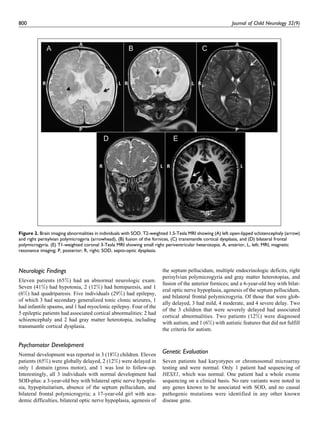

Figure 2. Brain imaging abnormalities in individuals with SOD. T2-weighted 1.5-Tesla MRI showing (A) left open-lipped schizencephaly (arrow)

and right perisylvian polymicrogyria (arrowhead), (B) fusion of the fornices, (C) transmantle cortical dysplasia, and (D) bilateral frontal

polymicrogyria. (E) T1-weighted coronal 3-Tesla MRI showing small right periventricular heterotopia. A, anterior, L, left; MRI, magnetic

resonance imaging; P, posterior; R, right; SOD, septo-optic dysplasia.